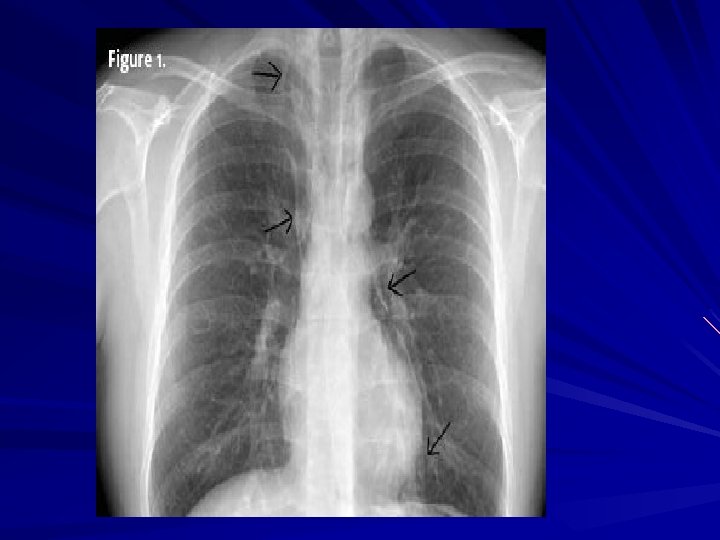

Diagnosis CXR may show air-fluid level Barium study quite dilated, and an airfluid level may be secondary to retained secretions. The classic finding is a gradual tapering at the end of the esophagus, similar to a bird's beak Upper endoscopy is the next diagnostic test in a patient with dysphagia or suspected achalasia

Symptoms and Diagnosis of an esophageal perforation may be made radiographically A chest roentgenogram may demonstrate a hydropneumothorax A contrast esophagram is done using barium for a suspected thoracic perforation and Gastrografin for an abdominal perforation.

Symptoms and Diagnosis Most perforations are found above the GEJ on the left lateral wall of the esophagus which results in a 10% false -negative rate in the contrast esophagram if the patient is not placed in the lateral decubitus position Chest CT shows mediastinal air and fluid at the site of perforation